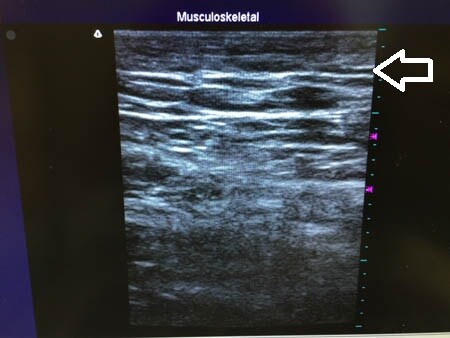

同様に右太もも正面。